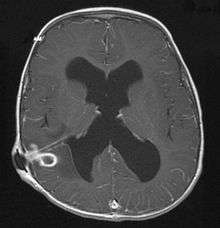

The diagnosis is established by a computed tomography (CT) (with contrast) examination. At the initial phase of the inflammation (which is referred to as cerebritis), the immature lesion does not have a capsule and it may be difficult to distinguish it from other space-occupying lesions or infarcts of the brain. Within 4–5 days the inflammation and the concomitant dead brain tissue are surrounded with a capsule, which gives the lesion the famous ring-enhancing lesion appearance on CT examination with contrast (since intravenously applied contrast material can not pass through the capsule, it is collected around the lesion and looks as a ring surrounding the relatively dark lesion). Lumbar puncture procedure, which is performed in many infectious disorders of the central nervous system is contraindicated in this condition (as it is in all space-occupying lesions of the brain) because removing a certain portion of the cerebrospinal fluid may alter the concrete intracranial pressure balances and causes the brain tissue to move across structures within the skull (brain herniation).

Ring enhancement may also be observed in cerebral hemorrhages (bleeding) and some brain tumors. However, in the presence of the rapidly progressive course with fever, focal neurologic findings (hemiparesis, aphasia etc.) and signs of increased intracranial pressure, the most likely diagnosis should be the brain abscess.